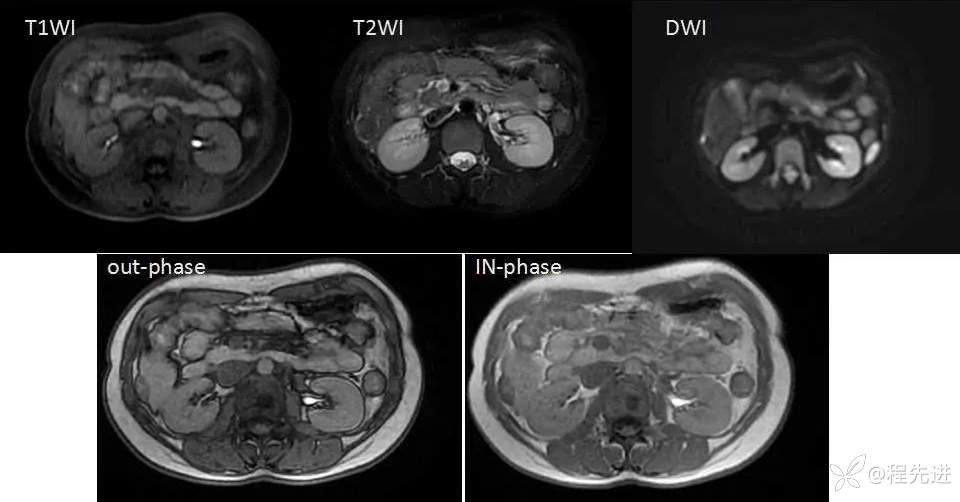

MRI检查: